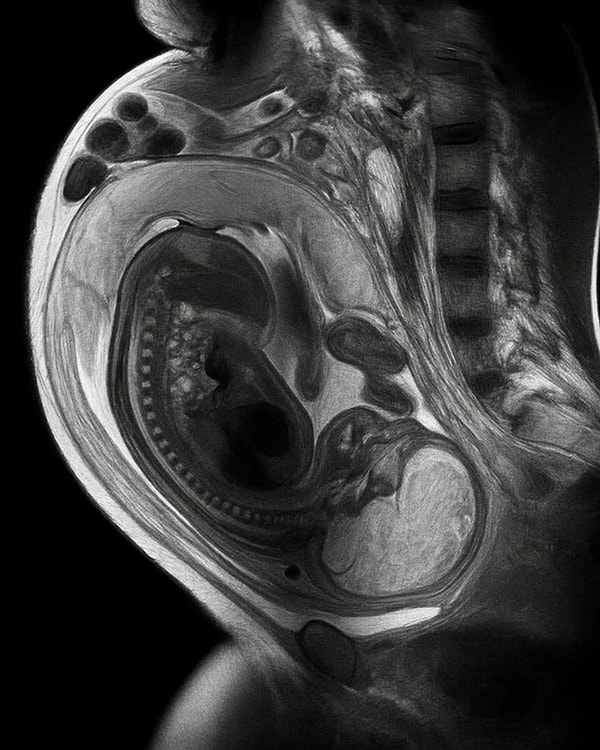

Anne ve çocuk arasındaki bağ, uzun yıllar boyunca yalnızca psikolojik ve duygusal bir olgu olarak nitelendirilse de modern tıp araştırmaları bu ilişkinin somut bir hücresel temeli olduğunu ortaya koyuyor. Mikrokimerizm olarak adlandırılan bu fenomen, gebelik süresince anne ile bebek arasında gerçekleşen çift yönlü hücre alışverişinin bireylerin yaşamı boyunca kalıcı izler bıraktığını kanıtlıyor.

Bilimsel literatürde ilk kez 1990’lı yıllarda tanımlanan fetal mikrokimerizm süreci, adını farklı canlı türlerinin özelliklerini barındıran mitolojik 'Chimera' figüründen alıyor. Gebelik sırasında fetüse ait kök hücreler ve lökositler, plasenta bariyerini aşarak annenin kan dolaşımına karışıyor. Yapılan patolojik incelemeler, bu hücrelerin doğumdan on yıllar sonra bile annenin beyin, kalp, karaciğer ve böbrek gibi hayati organlarında varlığını sürdürdüğünü gösteriyor. Leiden Üniversitesi bünyesinde gerçekleştirilen araştırmalarda, erkek çocuk dünyaya getirmiş kadınların doku örneklerinde Y kromozomuna rastlanması, bu hücrelerin kalıcılığını somutlaştırıyor.